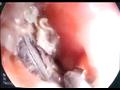

وقام فريق العمل في وحدة الجهاز الهضمي بعمل منظار للمريء وتبين وجود نصف جنيه بحالة صدأ كامل ما يدل على وجوده لفترة طويلة في هذا المكان ووجود تقرح حوله وتم استخراجه بالمنظار دون الحاجة للتدخل الجراحي وخرجت الطفلة من المستشفى بحالة جيدة.